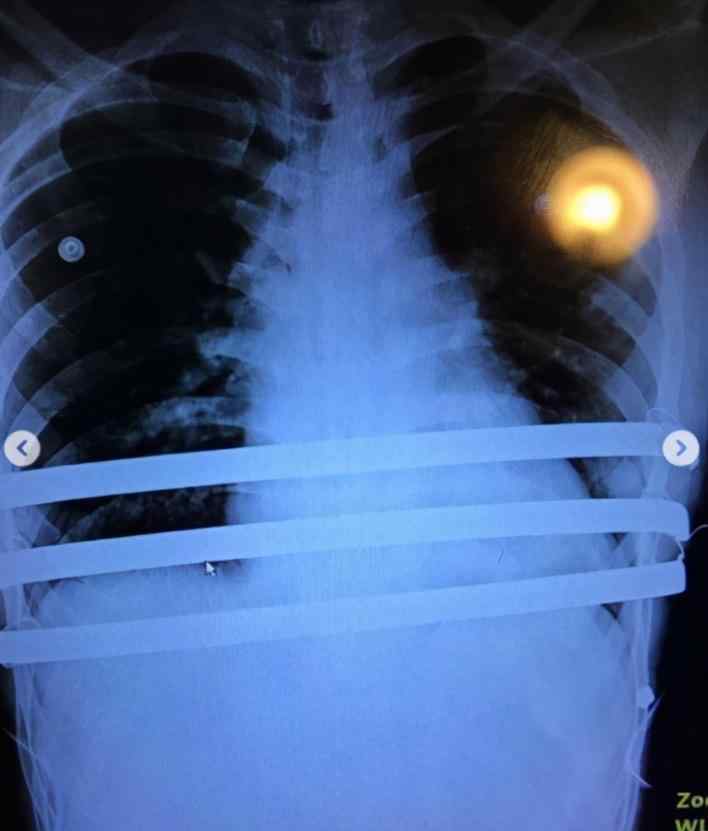

台湾当红男星楼君硕,其实有先天性疾病。2018年,楼君硕承认自己患有“先天性漏斗胸”,导致肺活量远小于常人。为了治疗,胸腔里放了三根长铁棒。

他晒过很多照片,包括依然在胸前的铁棒的x光照射,从胸前取出的三根长铁棒的照片,还有他躺在病床上,依然摆出一个手势报告安全的照片。

原来他在停工期间,去做了最后一次漏斗胸手术。他之所以在手术后报告自己安全,是怕粉丝担心。现在手术成功完成,他告诉大家最近停工的真正原因。